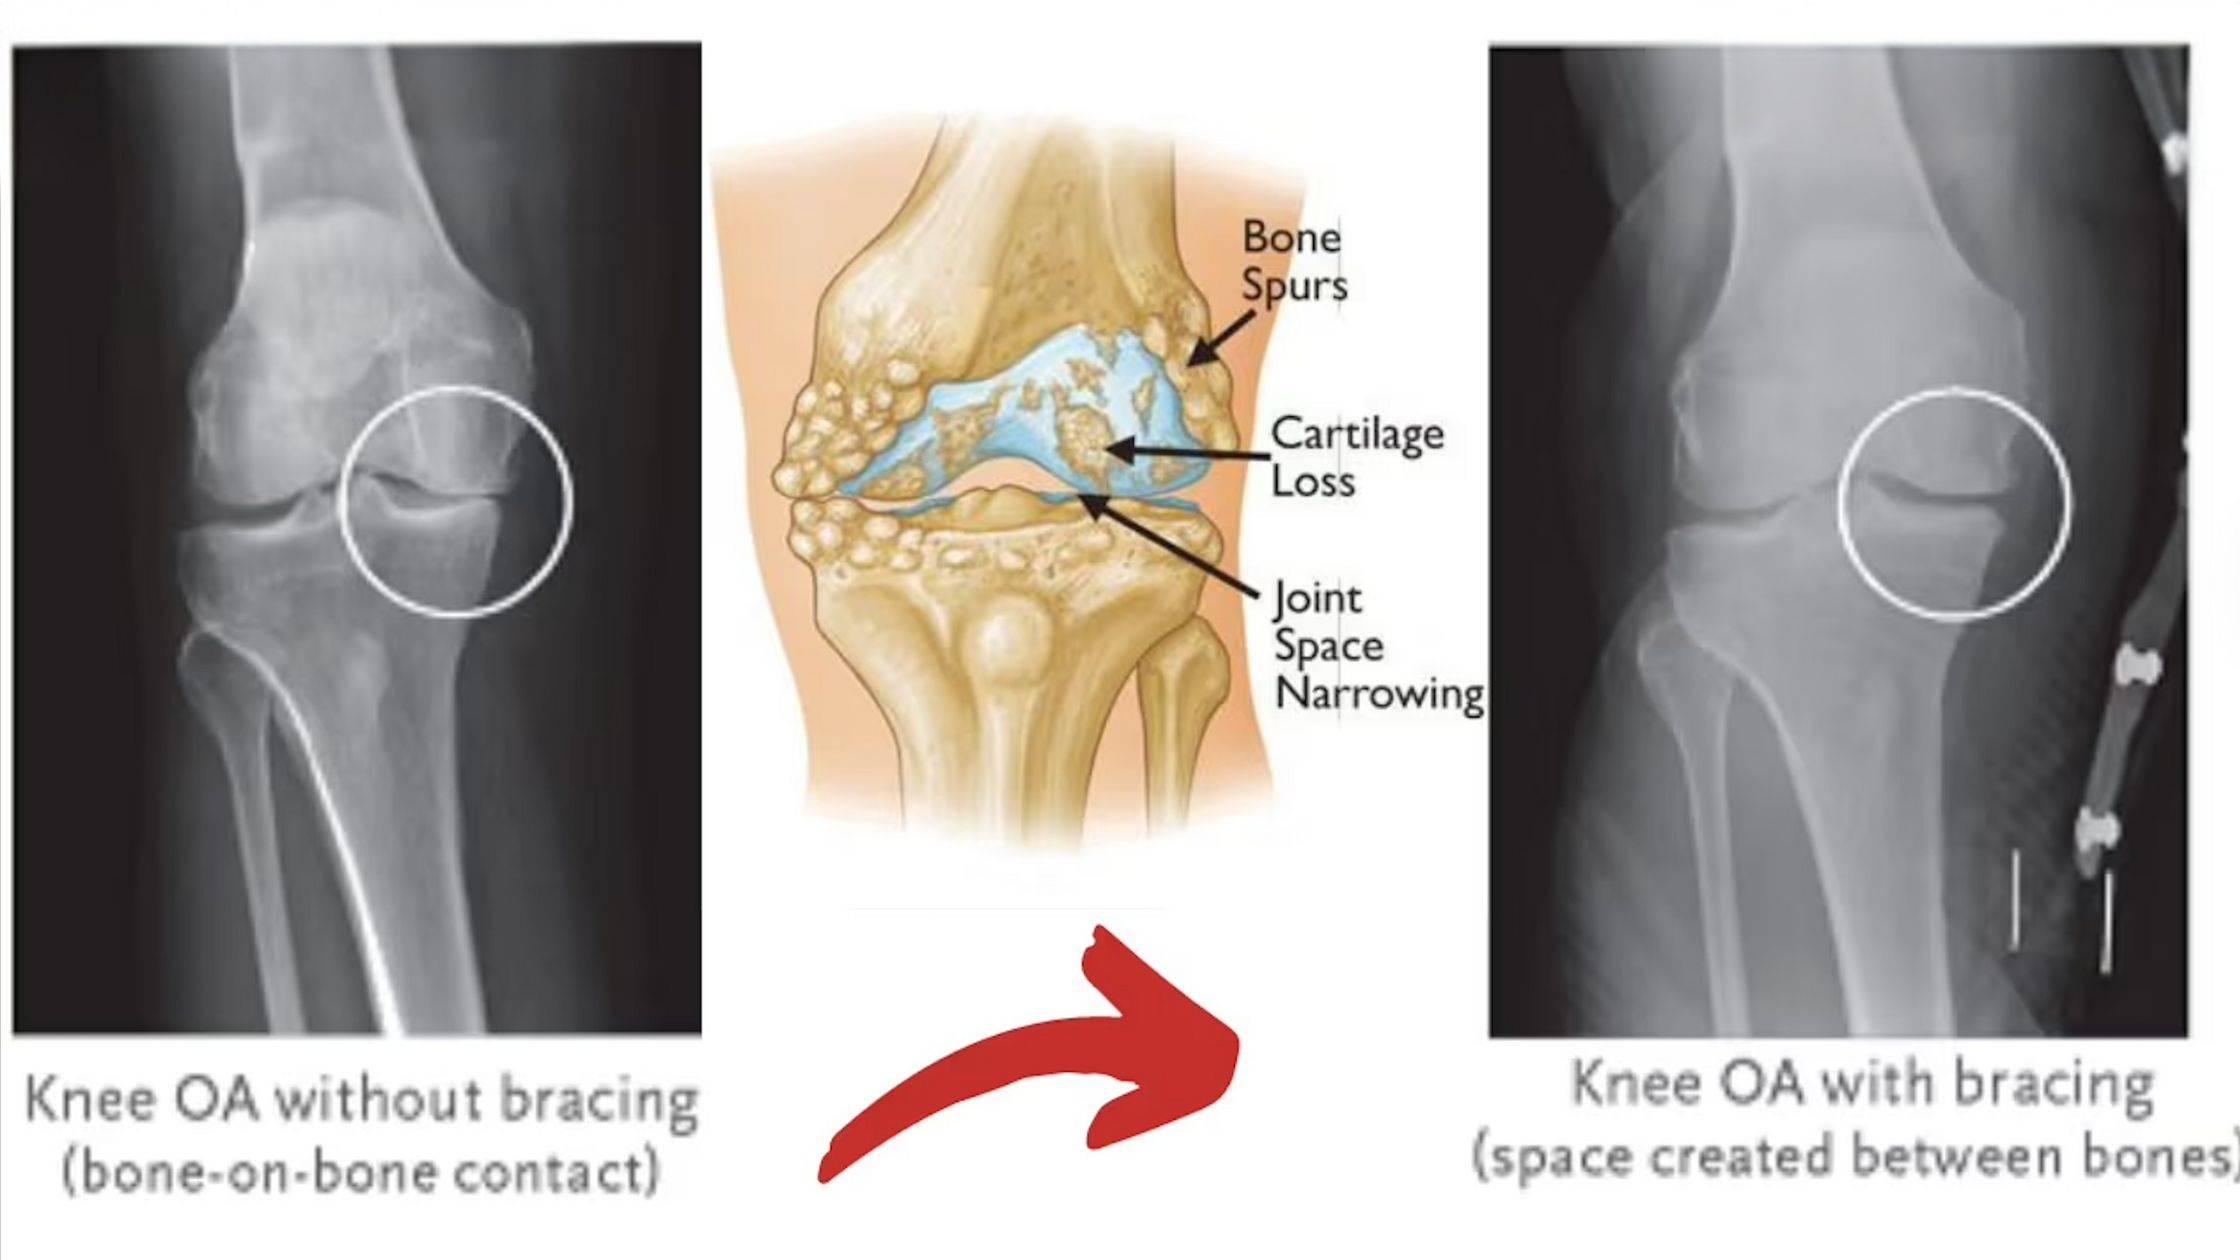

How Unloading Reduces Pressure on the Knee

"Clinicians often recommend unloader braces for relieving knee OA symptoms by redistributing pressure."

An OA (osteoarthritis) unloader knee brace is a medical brace designed to take pressure off the worn, painful side of your knee joint. It does this by gently shifting your body weight toward the healthier side of the knee, which can reduce pain and improve stability when you walk or stand.

“Bone-on-bone” pain on one side